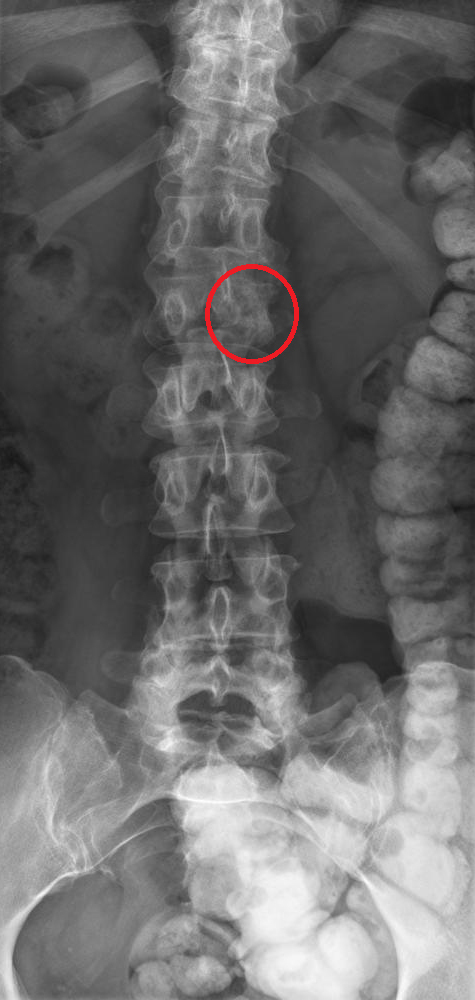

Son médecin traitant lui a prescrit de faibles doses de morphine, ce qui la soulage, et a fait réaliser l’élément suivant.

Question 11 - Concernant le tableau de la patiente (une ou plusieurs réponses exactes) :

Il s’agit d’un effet indésirable connu des inhibiteurs de l’aromatase, mais la perte du pédicule latéral gauche de L2 (vertèbre borgne) est en faveur d’une récidive.

L’aspect de vertèbre borgne est hautement évocateur d’une récidive (envahissement du pédicule latéral).

L’aspect de vertèbre borgne est fortement évocateur d’une récidive tumorale.

On doit compléter le bilan par une IRM afin de préciser les lésions rachidiennes, préciser le risque neurologique et discuter d’un geste à visée antalgique (chirurgie, radiothérapie, cimentoplastie…).

On doit également réaliser un bilan d’extension (TEP-scan ou scintigraphie osseuse et scanner thoraco-abdomino-pelvien [TAP]), afin de préciser l’étendue d’une probable récidive, et préciser la lésion à biopsier.